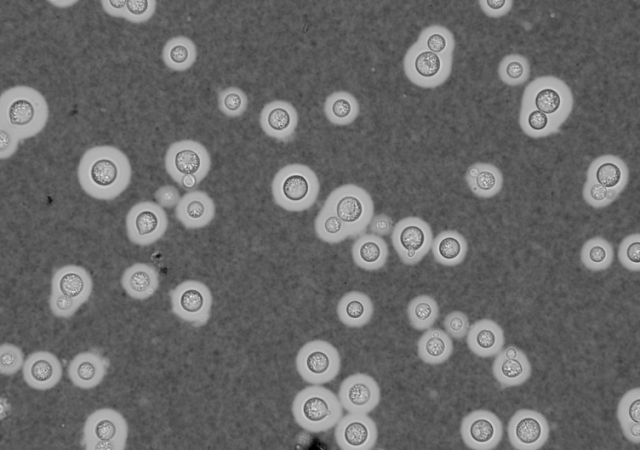

India Ink and Nigrosin stain are the acidic dyes used in negative staining. Either India ink or Nigrosin stain helps to stain capsules. Nigrosin stain is preferred over India stain because it can last more than one year, and no carbon particles will appear in the solution.

These stains detect capsule-forming fungi such as Cryptococcus neoformans which causes cryptococcal meningitis. The capsule appears as a clear halo against the dark background.